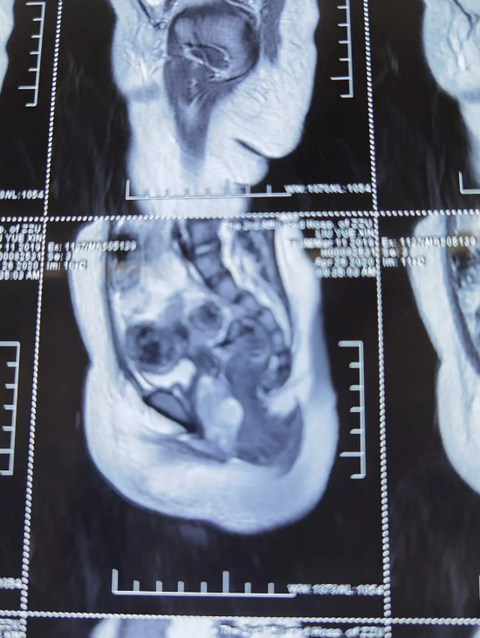

1岁女婴竟然来“月经”?确诊为阴道肿瘤,可能在2—4个月内死亡

1岁女婴检查出阴道肿瘤 悦悦是个1岁的女婴,20天前在玩学步车时,尿布上出现血迹,家长带她就近去诊所就诊后没再做进一步检查。然而,再次玩学步车时,悦悦的尿布上又出现了血迹,家人意识到问题的严重性,赶快带着她来到郑州大学第三附属医院就诊。 医生初步查看后,非常重视悦悦的病情,建议入院后做进一步检查,同时组织了由妇科、小儿外科、超声、影像、检验、血液肿瘤等科室专家参加的多学科会诊。 检查中发现,悦悦